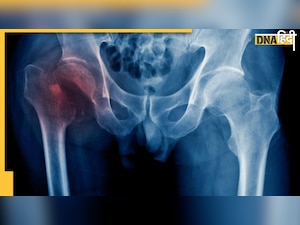

डीएनए हिंदी : टूटे हुए कूल्हे (Hip Fracture) का दर्द बयान करना मुश्किल होता है. घबराने वाली खबर यह है कि ऑस्टियोपोरोटिक हिप फ्रैक्चर इन दिनों वैश्विक समस्या बन गई है और इतना ही नहीं, आने वाले दो दशकों में इसके शिकार लगभग दोगुने लोग होंगे. दरअसल हांग - कांग विश्वविद्यालय के एक्सपर्ट ने ऑस्टियोपोरोटिक हिप फ्रैक्चर पर नई स्टडी की है. उनके अनुसार ऑस्टियोपोरोसिस और फ्रैक्चर के सबसे अधिक शिकार 85 साल से उम्र के लोग बनते हैं.  फ्रैक्चर जैसी समस्याओं से वे ही सबसे अधिक पीड़ित होते हैं, जिसपर रोक लगाने  सबसे अधिक है जिसको और ज़्यादा अध्ययन  और रोकथाम की आवश्यकता है.

अमेरिकन सोसायटी ऑफ़ बोन एंड मिनरल रिसर्च ने हाल में टेक्सस के ऑस्टिन में एक सेमिनार प्रस्तुत किया. इसे यूनिवर्सिटी ऑफ़ हांगकांग के असोसिएट प्रोफेसर चिंग लुंग चेउंग के नेतृत्व में पूरा किया गया. इस स्टडी में 19 देशों के 50 और उससे अधिक उम्र के मरीज़ों का सैंपल लिया गया. ये सभी हिप फ्रैक्चर (Hip Fracture) से पीड़ित थे. इस स्टडी में कुछ सनसनीखेज आंकड़े सामने निकल कर आए. गौरतलब है कि यूनाइटेड नेशन के एक अनुमान के मुताबिक 2050 तक पुरुषों का जीवन काल औसतन 75 साल की सीमा को पार कर जाएगा.

डॉ. चेउंग के अनुसार, “पुरुषों में ऑस्टियोपोरोसिस का लंबे समय से निदान और उपचार नहीं किया गया है. हमारे अध्ययन से यह भी पता चला है कि हिप फ्रैक्चर से पीड़ित होने के बाद पुरुषों में महिलाओं की तुलना में ऑस्टियोपोरोसिस विरोधी दवाएं लेने की संभावना 30% से 67% कम होती है.  इसलिए पुरुषों के हिप फ्रैक्चर की रोकथाम और उपचार पर अधिक ध्यान दिया जाना चाहिए.”

विशेषज्ञों के अनुसार अगर किसी के कूल्हे का फ्रैक्चर हुआ है तो इसके बाद फुल रिकवरी के लिए तीन से छह महीने तक का बेडरेस्ट बेहद जरूरी है. इससे हड्डी के ठीक होने की सम्भावना बढ़ जाएगी, अन्यथा यह शरीर को विकृत कर सकता है और पैर छोटे हो सकते हैं. बुजुर्गों में यह चलने की दिक्कत भी पैदा कर सकता है. इस खातिर ज़रूरी है कि ट्रीटमेंट गैप को कम किया जाए और फ्रैक्चर के बाद विशेष ध्यान रखा जाए.